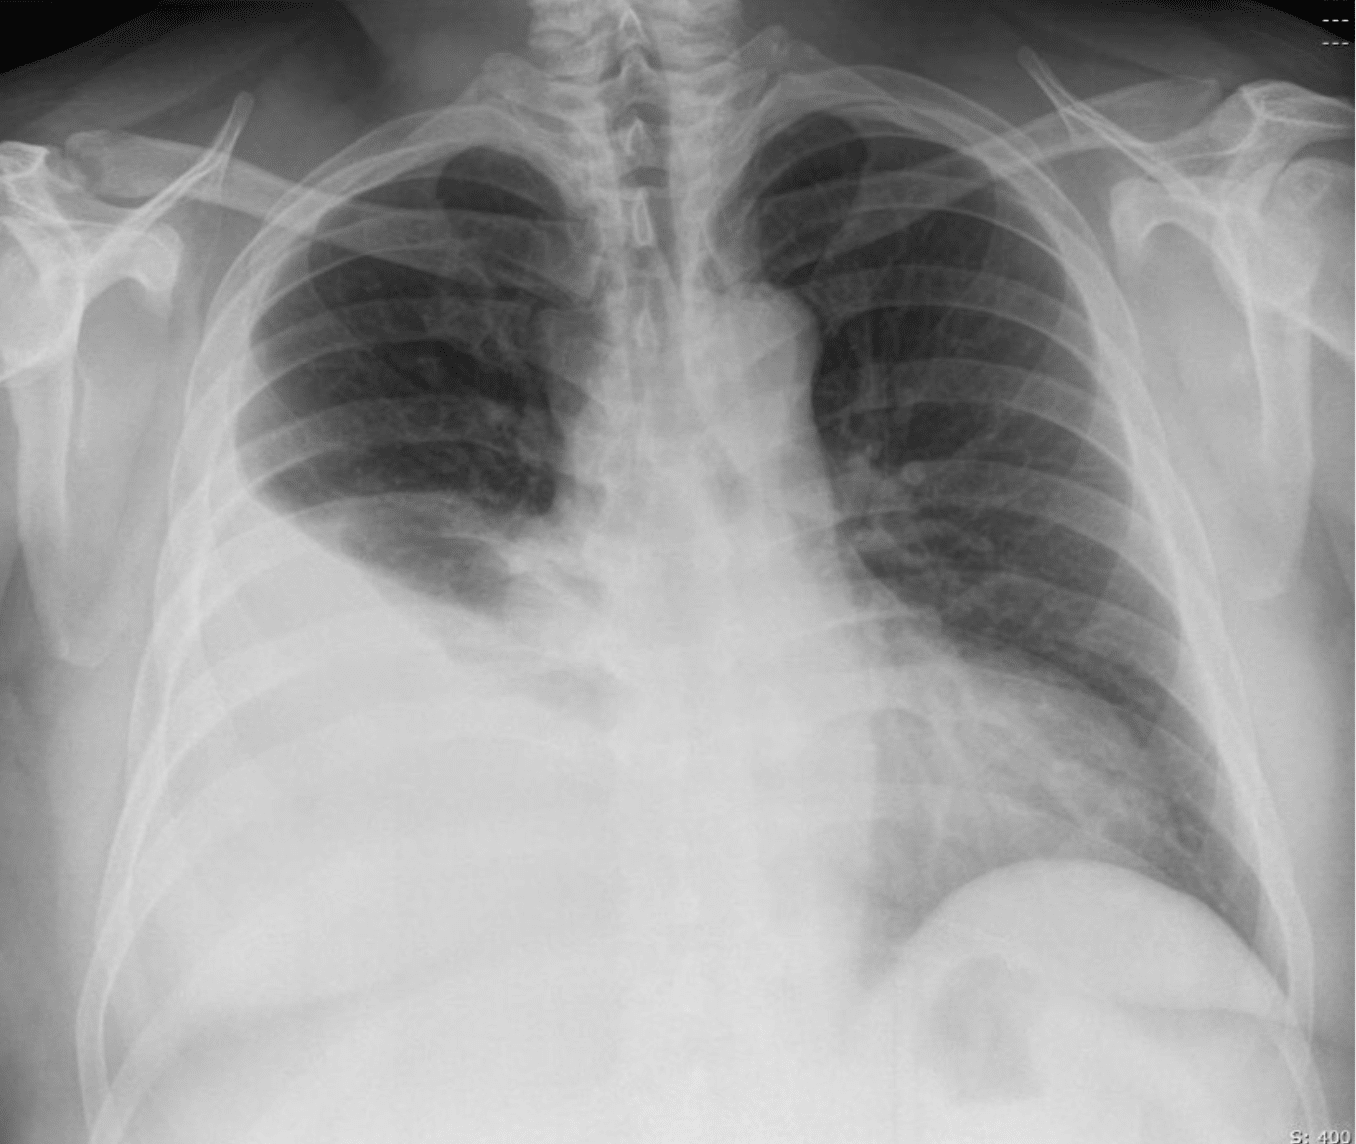

FFS: Pleural Effusion

Pleural effusion is the accumulation of fluid in the pleural space. Diagnosis is usually clinical and confirmed on CXR, though ultrasound or CT may be required. Pleural aspiration may be needed for diagnosis or to relieve dyspnoea.

- CXR: primary investigation for effusion